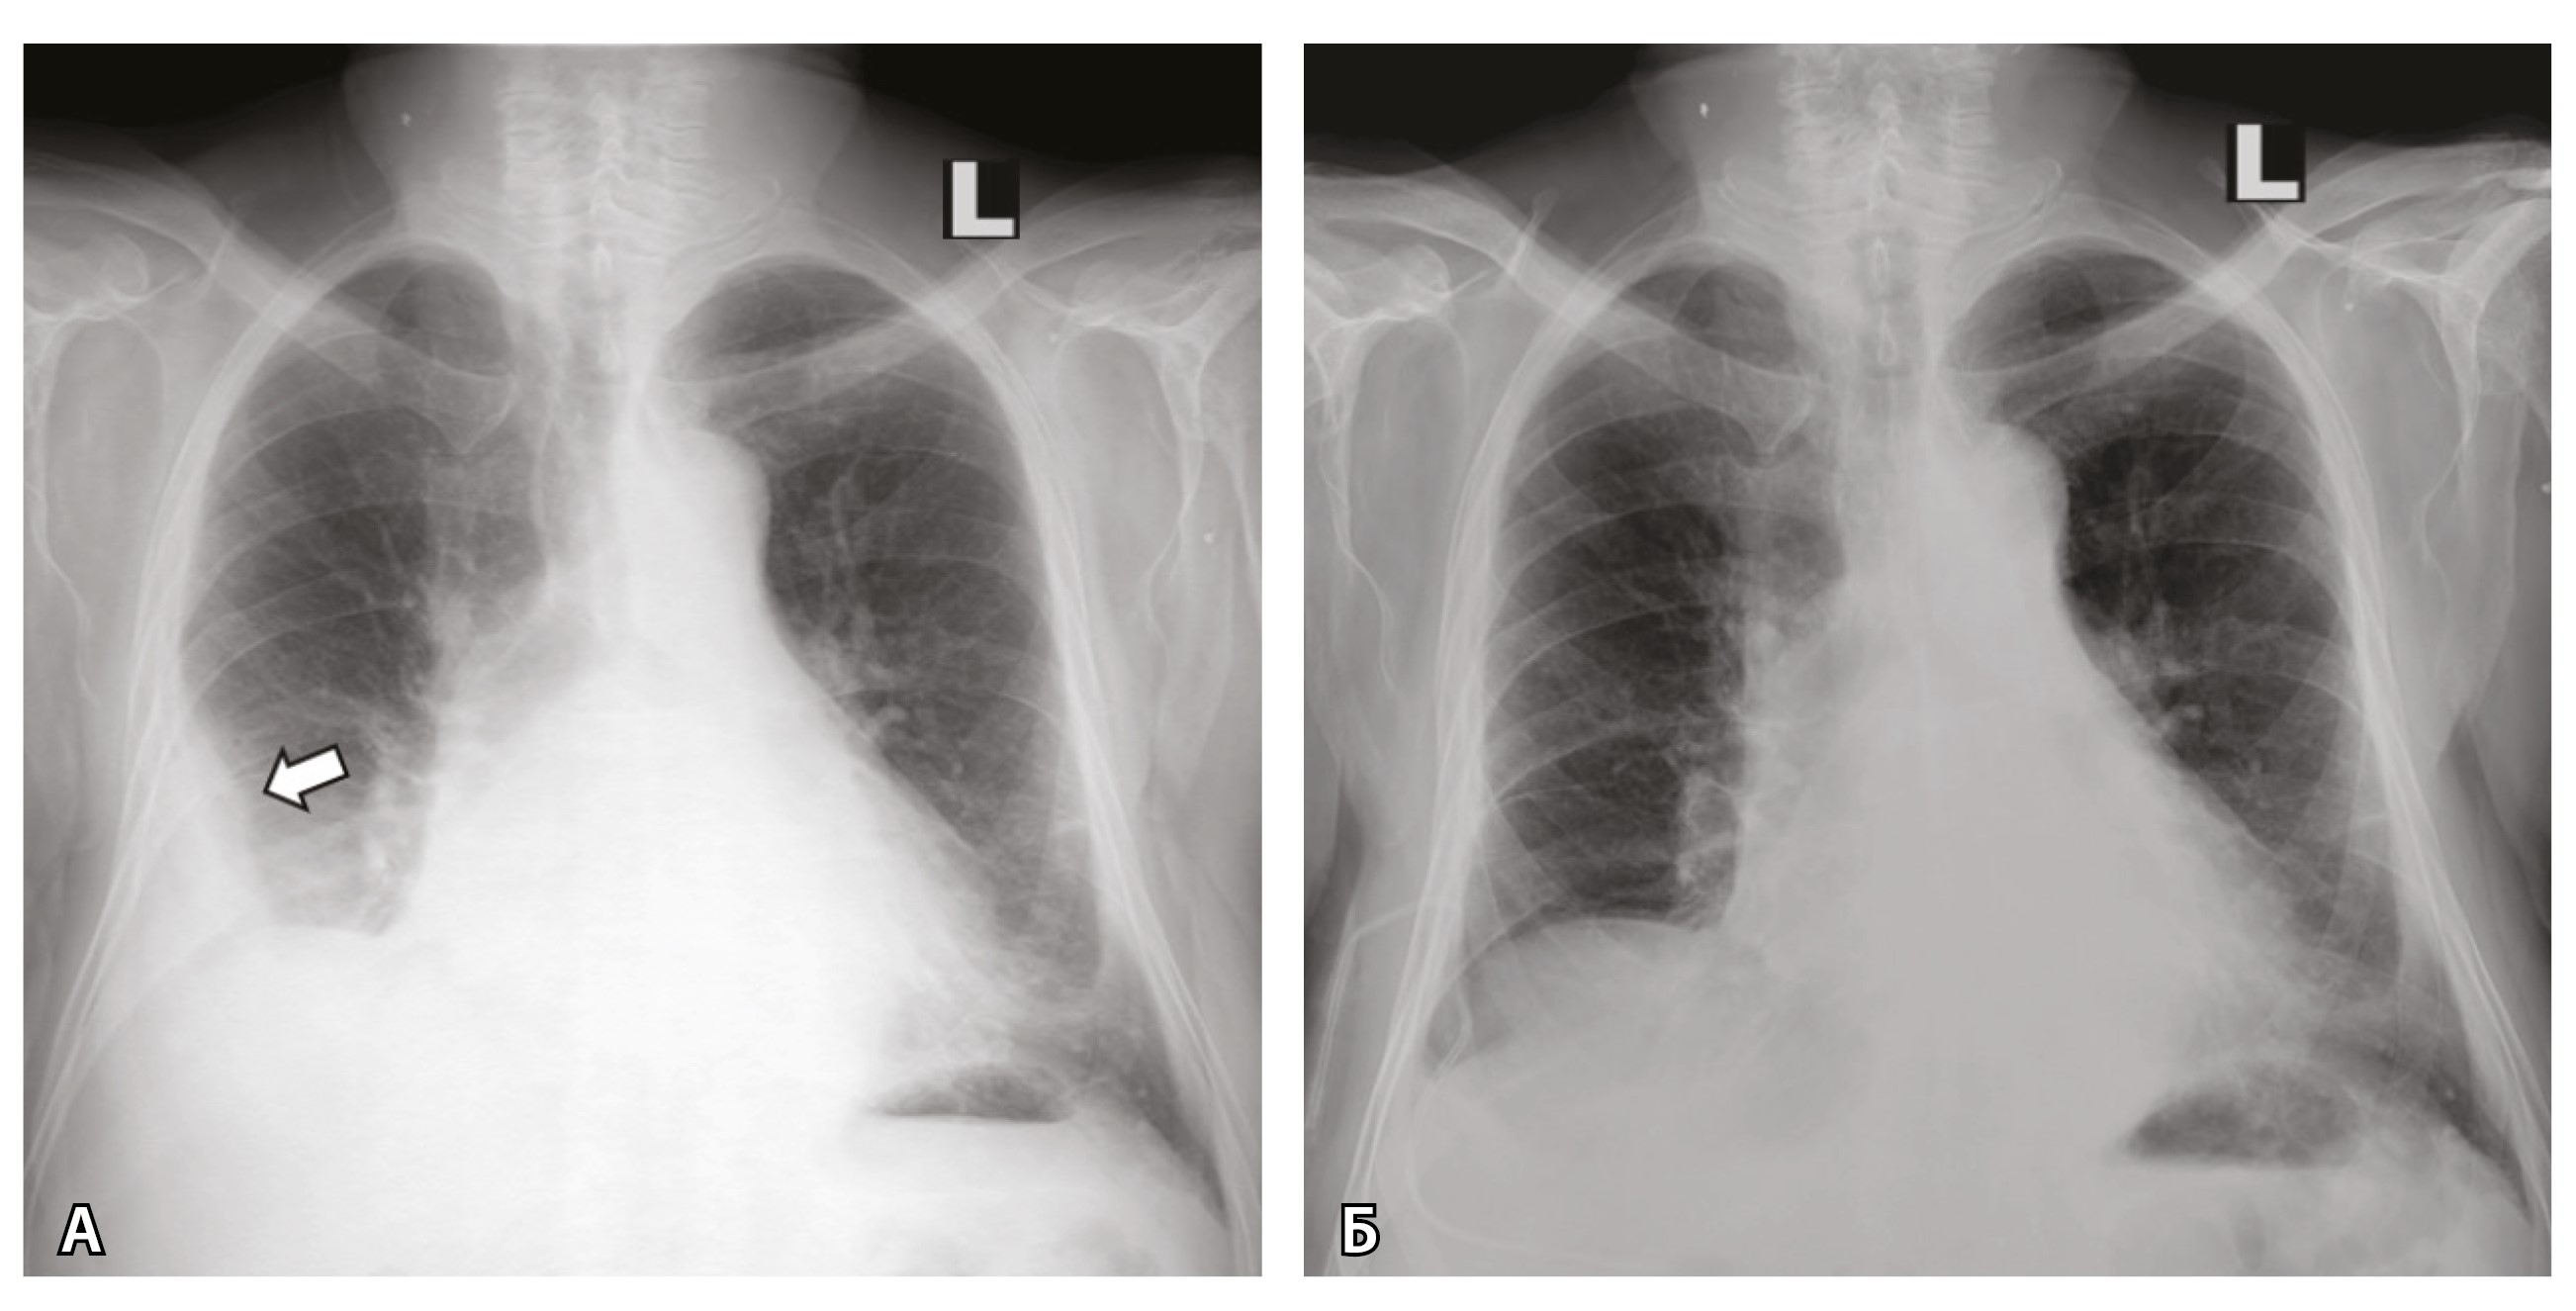

Кроме того, при УЗИ и рентгенографии 19.03.2024 выявлен правосторонний гидроторакс, расширение срединной тени. Проведено дренирование правой плевральной полости (рис. 2), эвакуировано 1700 мл соломенно-желтой жидкости. 20.03.2024 зафиксирован очередной пароксизм ФП (см. рис. 1).

Рис. 2. Рентгенограмма органов грудной клетки пациента до (А) и после (Б) плевральной пункции. Стрелкой указан косой верхний контур уровня жидкости в правой плевральной полости на уровне переднего отрезка 4-го ребра. Синусы слева прослеживаются. Тень сердца расширена